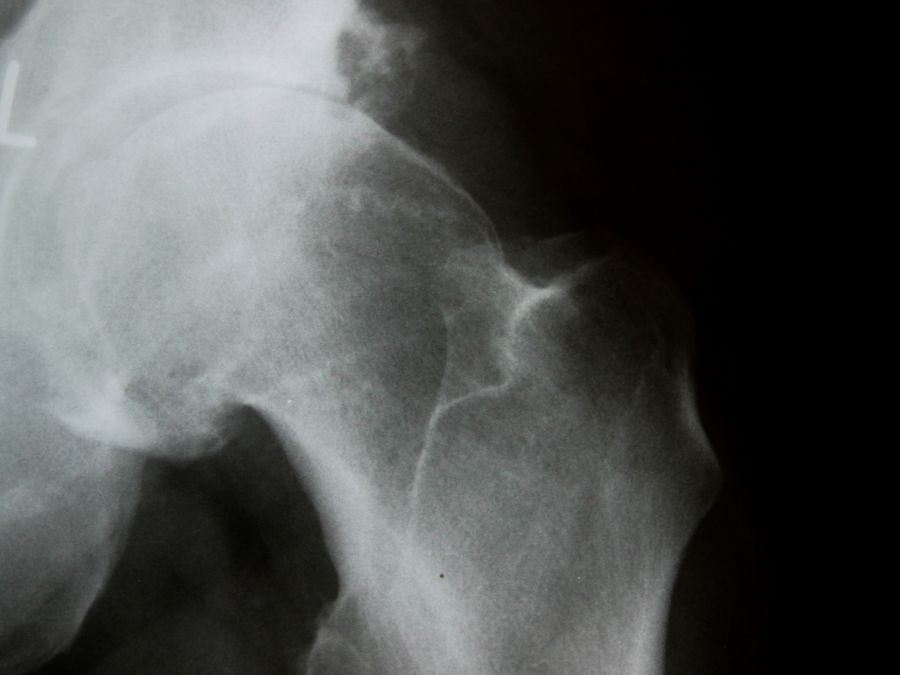

- Le radiografie mostrano una degenerazione avanzata con riduzione dello spazio articolare, osteofiti o deformazioni ossee.

Nella maggior parte dei casi, la protesi d’anca viene indicata per coxartrosi in fase avanzata, ma non è l’unica causa. Tra le condizioni che possono richiedere la sostituzione articolare troviamo:

- Artrosi primaria – legata al naturale invecchiamento e all’usura progressiva della cartilagine.

- Artrosi secondaria – conseguenza di traumi, fratture, displasia o alterazioni anatomiche che accelerano la degenerazione.

- Necrosi avascolare (osteonecrosi) della testa del femore – dovuta alla riduzione del flusso sanguigno, che porta al collasso osseo.